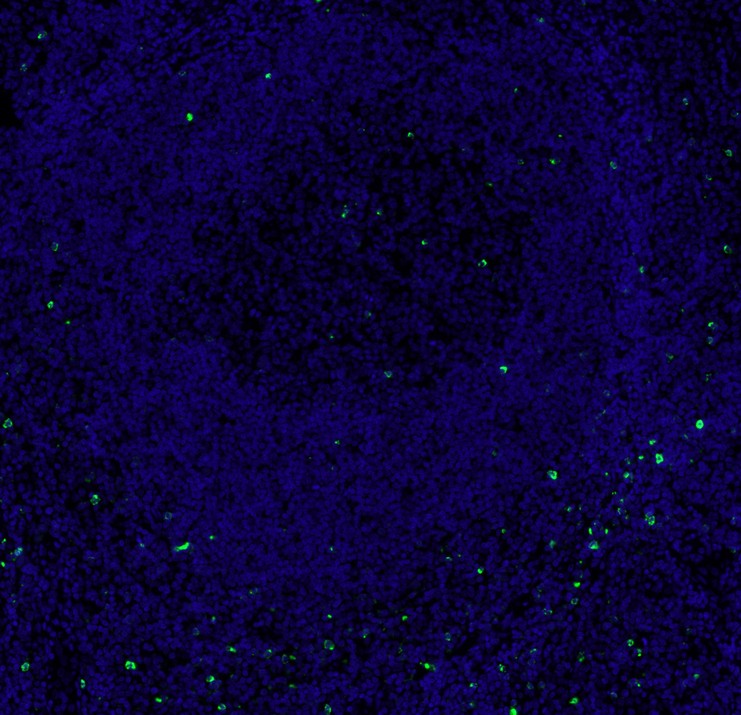

LAG-3 Recombinant Rabbit Monoclonal Antibody [PS01-33]

mIHC